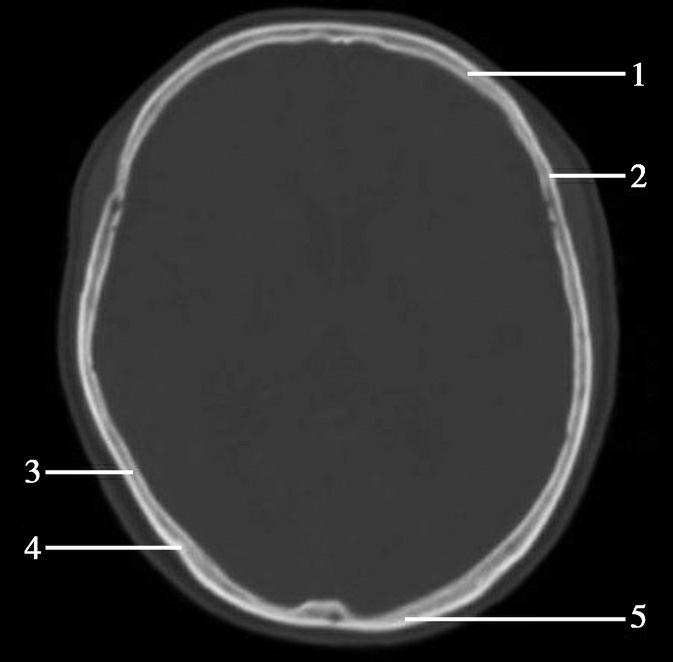

第三脑室正常成人前后径约12mm,左右宽约5mm,上下径也约为12mm。侧脑室后角两侧有时大小不等,右侧后角上下径约为38mm,左右径约为20mm;左侧后角上下径约为28mm,左右径约为15mm。测量双侧侧脑室前角间径与同平面脑横径的比值(R),正常平均值为30%。轻度扩大时为31%~39%,中度扩大为40%~46%,重度扩大时>47%。脑积水或脑萎缩等病理情况下脑室系统会扩大。不同年龄组正常脑室系统测量值存在差异,整体表现出测量值随着年龄增大而增大的趋势(图1-2-83、图1-2-84)。

图1-2-84 侧脑室测量

R=双侧侧脑室前角间径(a)/同平面脑横径(b)